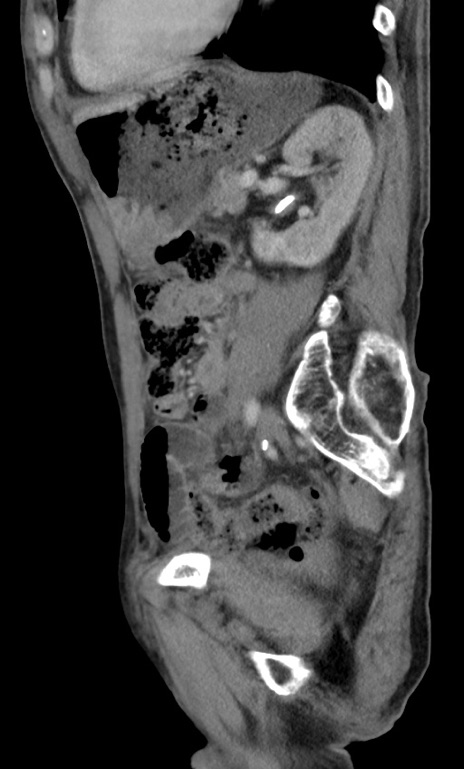

症例3(矢状断像)

【症例】 70歳代男性

【主訴】右鼠径部腫瘤、疼痛

【現病歴】本日朝より上記主訴あり、受診。

【既往歴】膀胱癌にて膀胱全摘、両側尿管皮膚瘻

【データ】WBC 5600、CRP 0.56